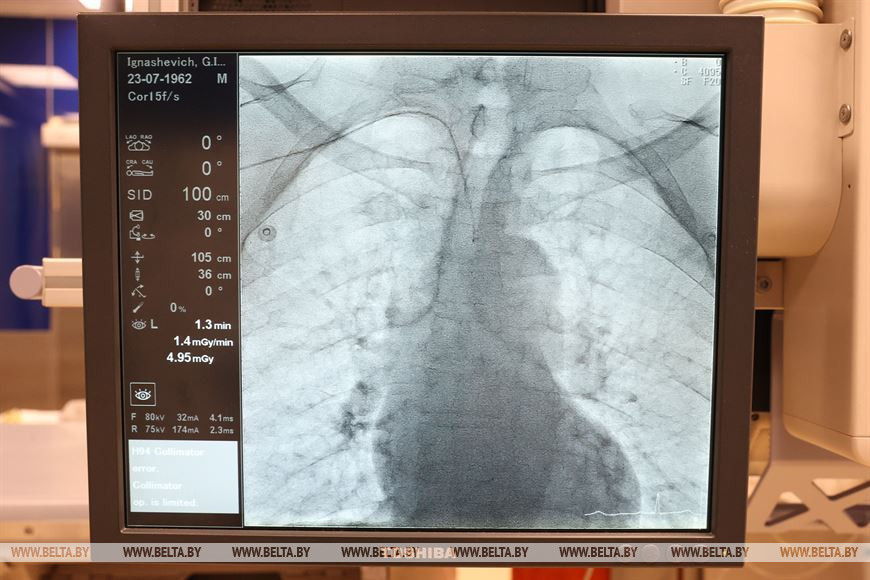

Рентгенэндоваскулярный хирург, заведующий кабинетом ангиографии и руководитель Южного межрайонного центра Минской области Александр Янукович гордится тем, что его отделение, став в 2014 году первым отделением районной эндоваскулярной хирургии в стране, сейчас является крупным специализированным центром. "Мы выполняем практически весь спектр вмешательств, который можно предложить пациентам на уровне районной больницы. Мы - это большой сплоченный коллектив, работающий уже 9 лет. У нас оказывается помощь пациентам южной части Минской области, а это 360 тыс. населения. Основная наша задача - оказание помощи пациентам с ишемической болезнью сердца, с ишемическим инсультом и цереброваскулярными болезнями. Мы также являемся межрайонным центром по имплантации электрокардиостимуляторов, этой программой занимаемся в течение последних двух лет. Прооперировано уже порядка 150 пациентов. Они обслуживаются у нас же - на базе центра организован кабинет контроля кардиостимуляторов. Также с гордостью мы можем сказать, что являемся единственным центром районного уровня в стране, который выполняет вмешательства по ишемическому инсульту, вмешательства на сосудах шеи. Кроме того, являемся межрайонным центром по сосудистой хирургии. Поэтому мы многофункциональная, многопрофильная, многоуровневая структура. Например, сегодня у нас 6 плановых операций, две из них - это постановка кардиостимулятора, три пациента с ишемической болезнью сердца, один из них готовится к кардиологическому вмешательству в РНПЦ кардиологии, два - с перенесенным в прошлом инфарктом. В любой момент к нам могут доставить пациента с ишемическим инсультом, например, а это уже нейрохирургическая помощь. В среднем за сутки мы обслуживаем 10 пациентов. С нового года через нас прошло уже порядка 900 пациентов, и такими темпами за год мы получим цифру в 1-1,6 тыс. пациентов", - рассказал Александр Янукович.

В отделении работают четыре хирурга, трое из них - высшей категории и один - первой. С осени врачей станет пять. "На подготовке у нас находится еще один врач. Да, нагрузка достаточно большая, но вполне терпимая, и от дополнительной работы мы никогда не отказываемся. По остальному персоналу у нас тоже хороший комплект. Очередей на выполнение плановых операций у нас нет. Для выполнения коронарографии достаточно 5-7 дней, это ожидание, как правило, занимает подготовка, приезд пациента и оформление. Мы выполняем операции с сегодня на завтра, то есть сегодня пациент лег, завтра выполнена операция, если все хорошо, то через день едет домой. То же самое с кардиостимуляторами, очередей на имплантацию нет", - отметил заведующий кабинетом ангиографии.